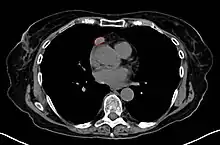

A chest CT-scan showing a thymoma (red circle)

A chest X-ray may identify widening of the mediastinum suggestive of thymoma, but computed tomography (CT) or magnetic resonance imaging (MRI) are more sensitive ways to identify thymomas and are generally done for this reason.[38] MRI of the cranium and orbits may also be performed to exclude compressive and inflammatory lesions of the cranial nerves and ocular muscles.[39]

As thymomas are seen in 10% of all people with the MG, people are often given a chest X-ray and CT scan to evaluate their need for surgical removal of their thymus and any cancerous tissue that may be present.[18][37] Even if surgery is performed to remove a thymoma, it generally does not lead to the remission of MG.[49] Surgery in the case of MG involves the removal of the thymus, although in 2013 there was no clear indication of any benefit except in the presence of a thymoma.[53] A 2016 randomized controlled trial, however, found some benefits.[54]